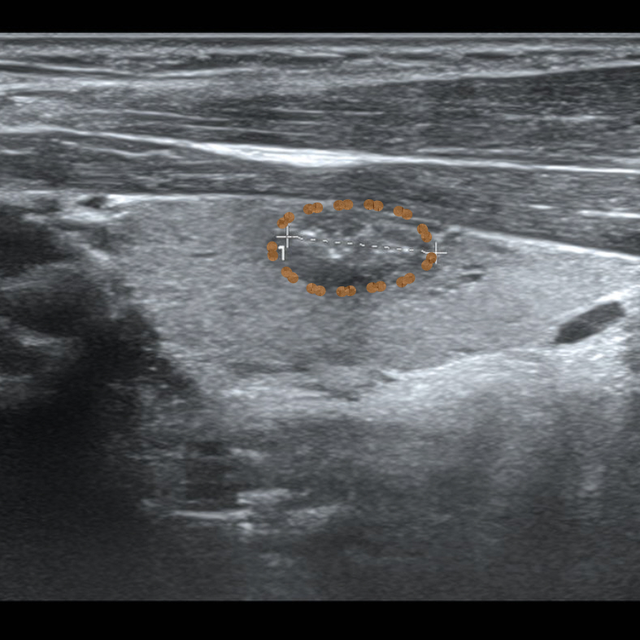

14岁女生小黄因小腹不适由母亲带至昆山市中医医院妇科就诊,超声检查后发现右附件区有一个8.0*7.2cm的巨大囊肿。由于正值初三备考的关键时期,如何解决囊肿还不能耽误复习迎考,这成了选择手术方式的关键点。

在医生和家属的再三沟通下,家属决定选择超声引导下介入治疗。

▲小黄的影像学检查

超声介入团队联合妇科对患者进行全面综合评估后,认为超声引导下抽液硬化治疗是其最佳选择。待一系列术前常规检查后,在局部浸润麻醉下进行囊肿穿刺抽液硬化治疗。

治疗过程中,利用一步法置入一根“6F的猪尾巴管”,共抽出淡黄色液体220ml,部分送检行脱落细胞学检查。后用生理盐水对囊腔进行多次冲洗达清亮后抽出,注入40ml聚桂醇反复冲洗后留置,隔日抽出囊液50ml,此时囊液显示为酒红色,证明硬化效果较好,继续留置2日待负压球内基本无引流液后拔管。

整个治疗过程顺利,患者无明显不适,未影响其正常复习迎考。三月后腹部超声检查,右附件区囊肿已完全吸收。